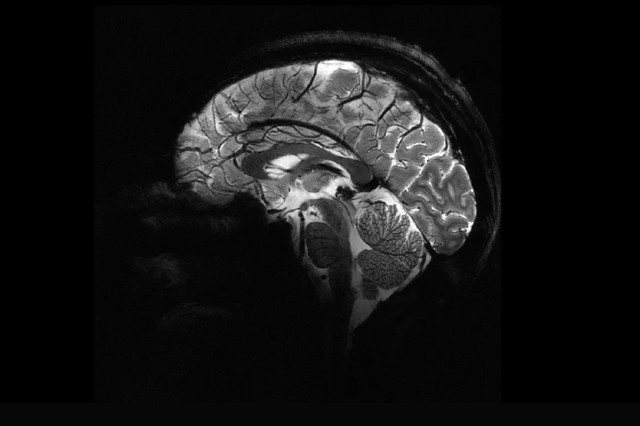

Mi az Alzheimer-kór? Tünetek, okok, kezelések

Az Alzheimer-kór az időskori elbutulás (demencia) leggyakoribb oka, a betegség lefolyása általában 8‑12 év.